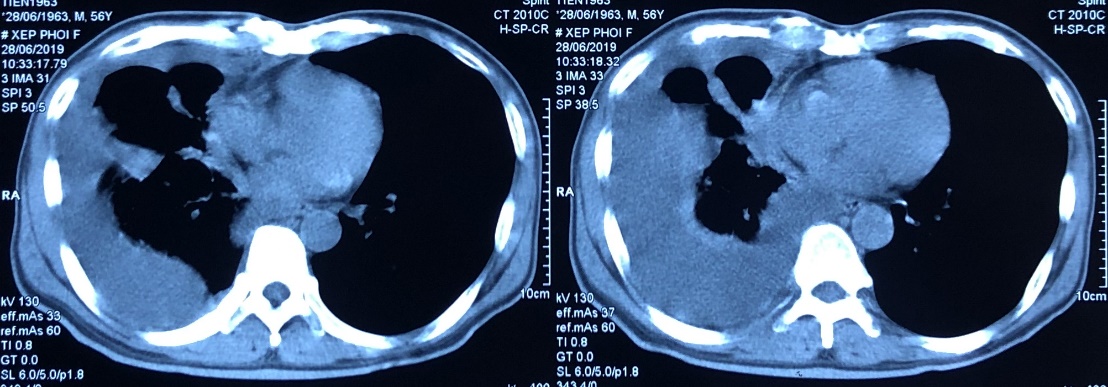

– Chụp cộng hưởng từ sọ não: Tổn thương xương trán phải kích thước 19x18mm, ngấm thuốc mạnh sau tiêm theo dõi tổn thương thứ phát. Không thấy hình ảnh tổn thương thứ phát nhu mô não.

Hình 2: Hình ảnh chụp cộng hưởng từ sọ não: tổn thương thứ phát xương sọ não (vòng tròn vàng)